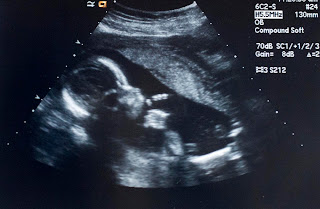

Here is a picture from the last ultrasound right before the Amnio.

He is weighing in at 1.1 Lbs. He is kind of on the big side.